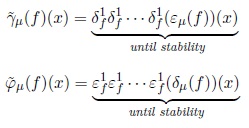

Viscous opening and closing utilize the parameters λ and μ. The ελ(f) and δλ(f) are used to detect those components that can be separated. To illustrate this situation consider the image in Fig. 2. Original image is presented in Fig. 2(a). In Fig. 2(b), the erosion size λ = 5 disconnects chained components; posteriorly in Fig. 2(c) the opening by reconstruction eliminates the components of size minor than μ — λ = 3 while the remaining components are maintained unchanged. Finally, in Fig. 2(d) the dilated image with λ = 5 recover the size of the original components but now they are disconnected. The components that do not support the erosion and the opening by reconstruction are merged with the background.